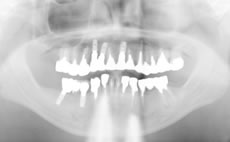

あごの骨にチタン性の人工歯根を埋め込み、噛む力を再生させる治療法です。

チタン性のインプラントは1965年にスウェーデンで開発され、日本では1996年頃から歯を失った部分の治療の選択肢としてインプラントが普及してきました。現在世界中で約100種類のインプラントがあり、日本では20種類以上のインプラントが国に認可されています。

※当院はアストラテックインプラントおよびオクタフィックスインプラントを使用しています。